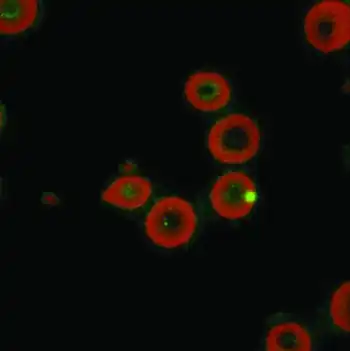

The disease is caused by the bacterium Bartonella quintana (older names: Rochalimea quintana, Rickettsia quintana), found in the stomach walls of the body louse.[3] Bartonella quintana is closely related to Bartonella henselae, the agent of cat scratch fever and bacillary angiomatosis.